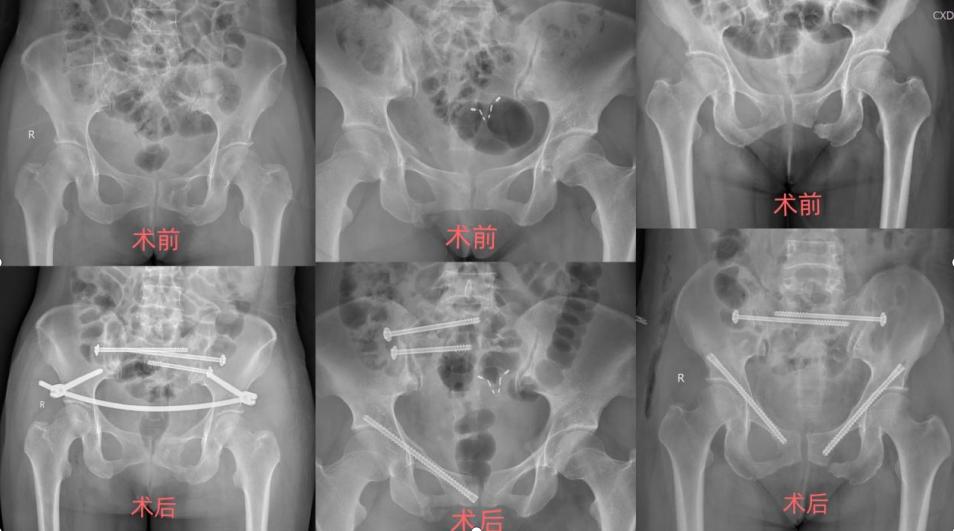

• 市三医院骨科:骨盆骨折微创手术“撑”起重伤小女孩

市三医院骨科:骨盆骨折微创手术“撑”起重伤小女孩 2021-09-28